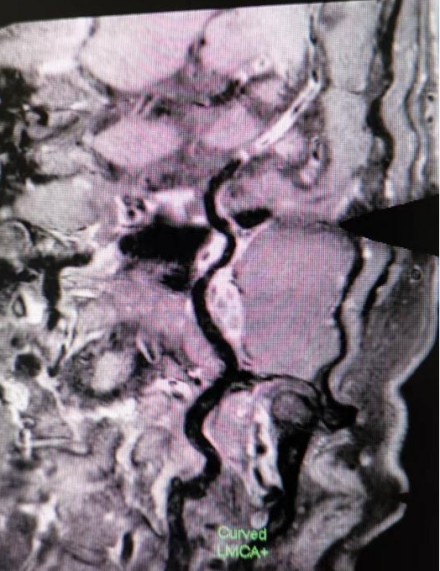

4招丨发现血管炎性病变

c942acd936317f3ed8349105fac4e327.png

左图T1W平扫见大脑中动脉M2段管壁增厚明显并呈等高信号,右图T1W增强后见管壁强化明显,提示该处有活动性炎症。

91afb25b92d13a6bf5254e21724c0d78.png

3D曲面重建后更直观明确血管壁炎症的位置和情况。